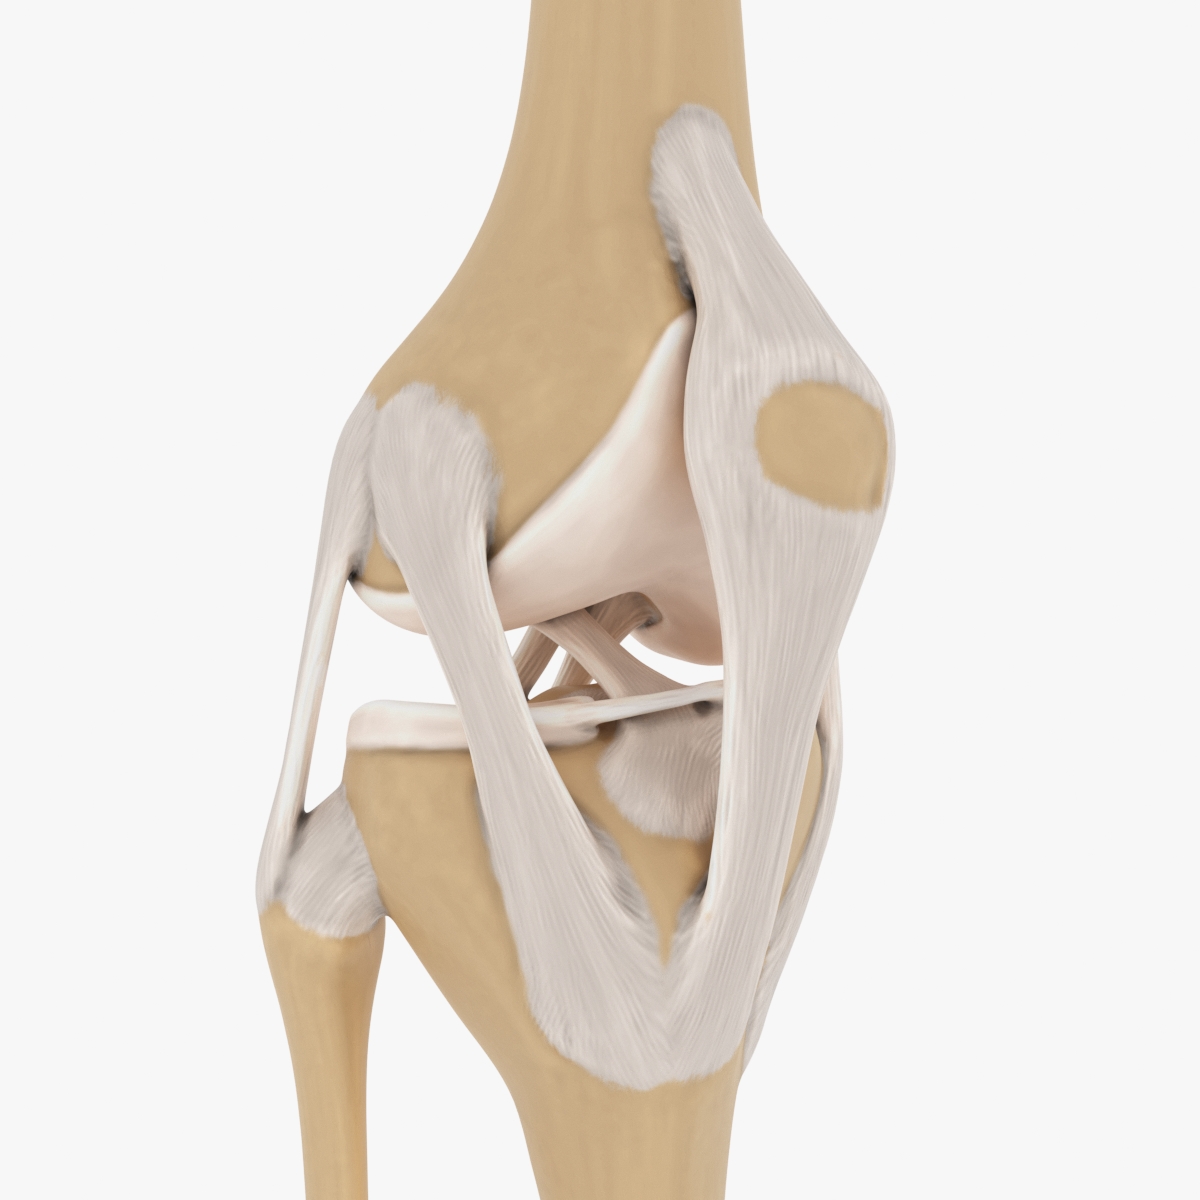

Knee 3D Model $60 - .c4d - Free3D

free3d.comAnatomical Medical Knee Joint With Ligaments Model, Life-size, For

free3d.comAnatomical Medical Knee Joint With Ligaments Model, Life-size, For

www.fruugo.es3d Anatomically Correct Knee Model

www.fruugo.es3d Anatomically Correct Knee Model

3d Anatomically Correct Knee Model

www.turbosquid.comknee anatomically correct

www.turbosquid.comknee anatomically correct

Knee Joint 3D Model | CGTrader

www.cgtrader.comknee cgtrader science

www.cgtrader.comknee cgtrader science

pikbest.com3d Anatomically Correct Knee Model

pikbest.com3d Anatomically Correct Knee Model

Dynamic Knee Model - Modeling Anatomical Accuracy

dynamicdiscdesigns.comFlüssigkeit Im Knie – Heilpraxis